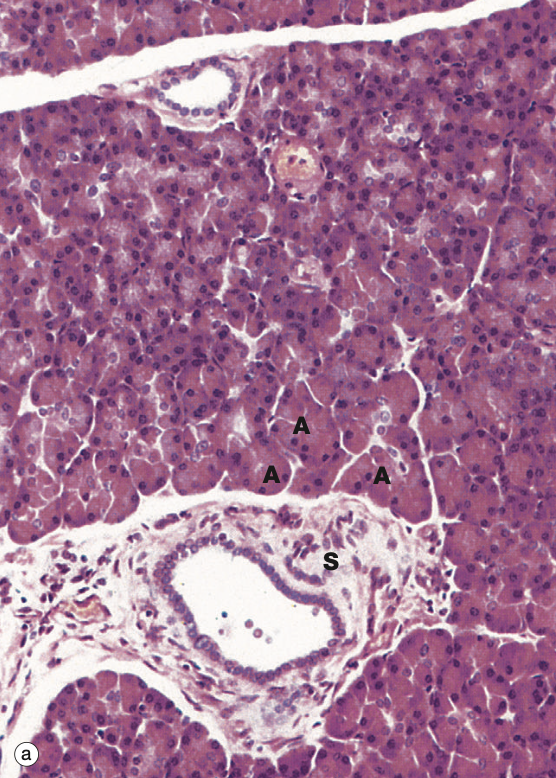

Identify the Organ and Structures?

Liver; Lobule w/ Central vein, surr by Hepato and Sinu, Portal triads in corners

D = Pv on top, Bd on left, Ha on right, C = Bd

Liver;

1 = Bile duct

2 = Hepatocytes

3 = Sinusoids

4 = Portal Vein

5 = Hepatic arteriole